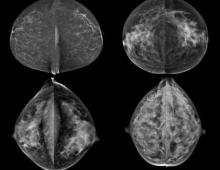

http://glossary.itnonline.com/3d-mammographyHologic Inc. announced that a groundbreaking new study published in Radiology, the Radiological Society of North America scientific journal, found that the addition of three dimensional (3-D) mammography (breast tomosynthesis) screening technology to a 2-D breast screening exam significantly increased cancer detection while reducing the number of false positives.

According to a new market research report "Breast Imaging Technologies Market (Digital Mammography,3D Breast Tomosynthesis, Breast MRI, Breast Ultrasound, Molecular Breast Imaging, Optical Imaging, PET/CT/PEM Modalities) Technology and Market Analysis & Global Forecasts to 2017" is an attempt to showcase the market impact of current and emerging breast imaging technologies having excellent growth potential in the coming five years. The technologies profiled in the report are segmented into Ionizing breast imaging modalities and Non-Ionizing breast imaging technologies on basis of radiation. Ionizing breast imaging modalities include Mammography, 3D Breast Tomosynthesis, Cone beam Computed Tomography (CBCT), Positron Emission Mammography (PEM), Molecular Breast Imaging (MBI), Positron Emission Tomography (PET) and Breast Specific Gamma Imaging (BSGI). The various Non-ionizing modalities for breast screening covered in the report are Breast MRI, Optical Imaging, Breast thermography and Breast Ultrasound.